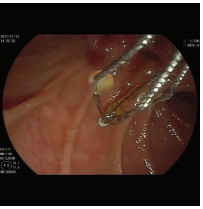

Endoscopic retrograde cholangiopancreatography combined with Spyglass in diagnosis of common bile duct papillary myxoma: A case report

Xuan DING, Linheng WANG, Gui JIANG, Yifei YUN, Xinyu LU, Yupu YAO

2021, 37(12): 2902-2904. DOI: 10.3969/j.issn.1001-5256.2021.12.034

Abstract(1315) HTML (221) PDF (2331KB)(47)

Abstract: